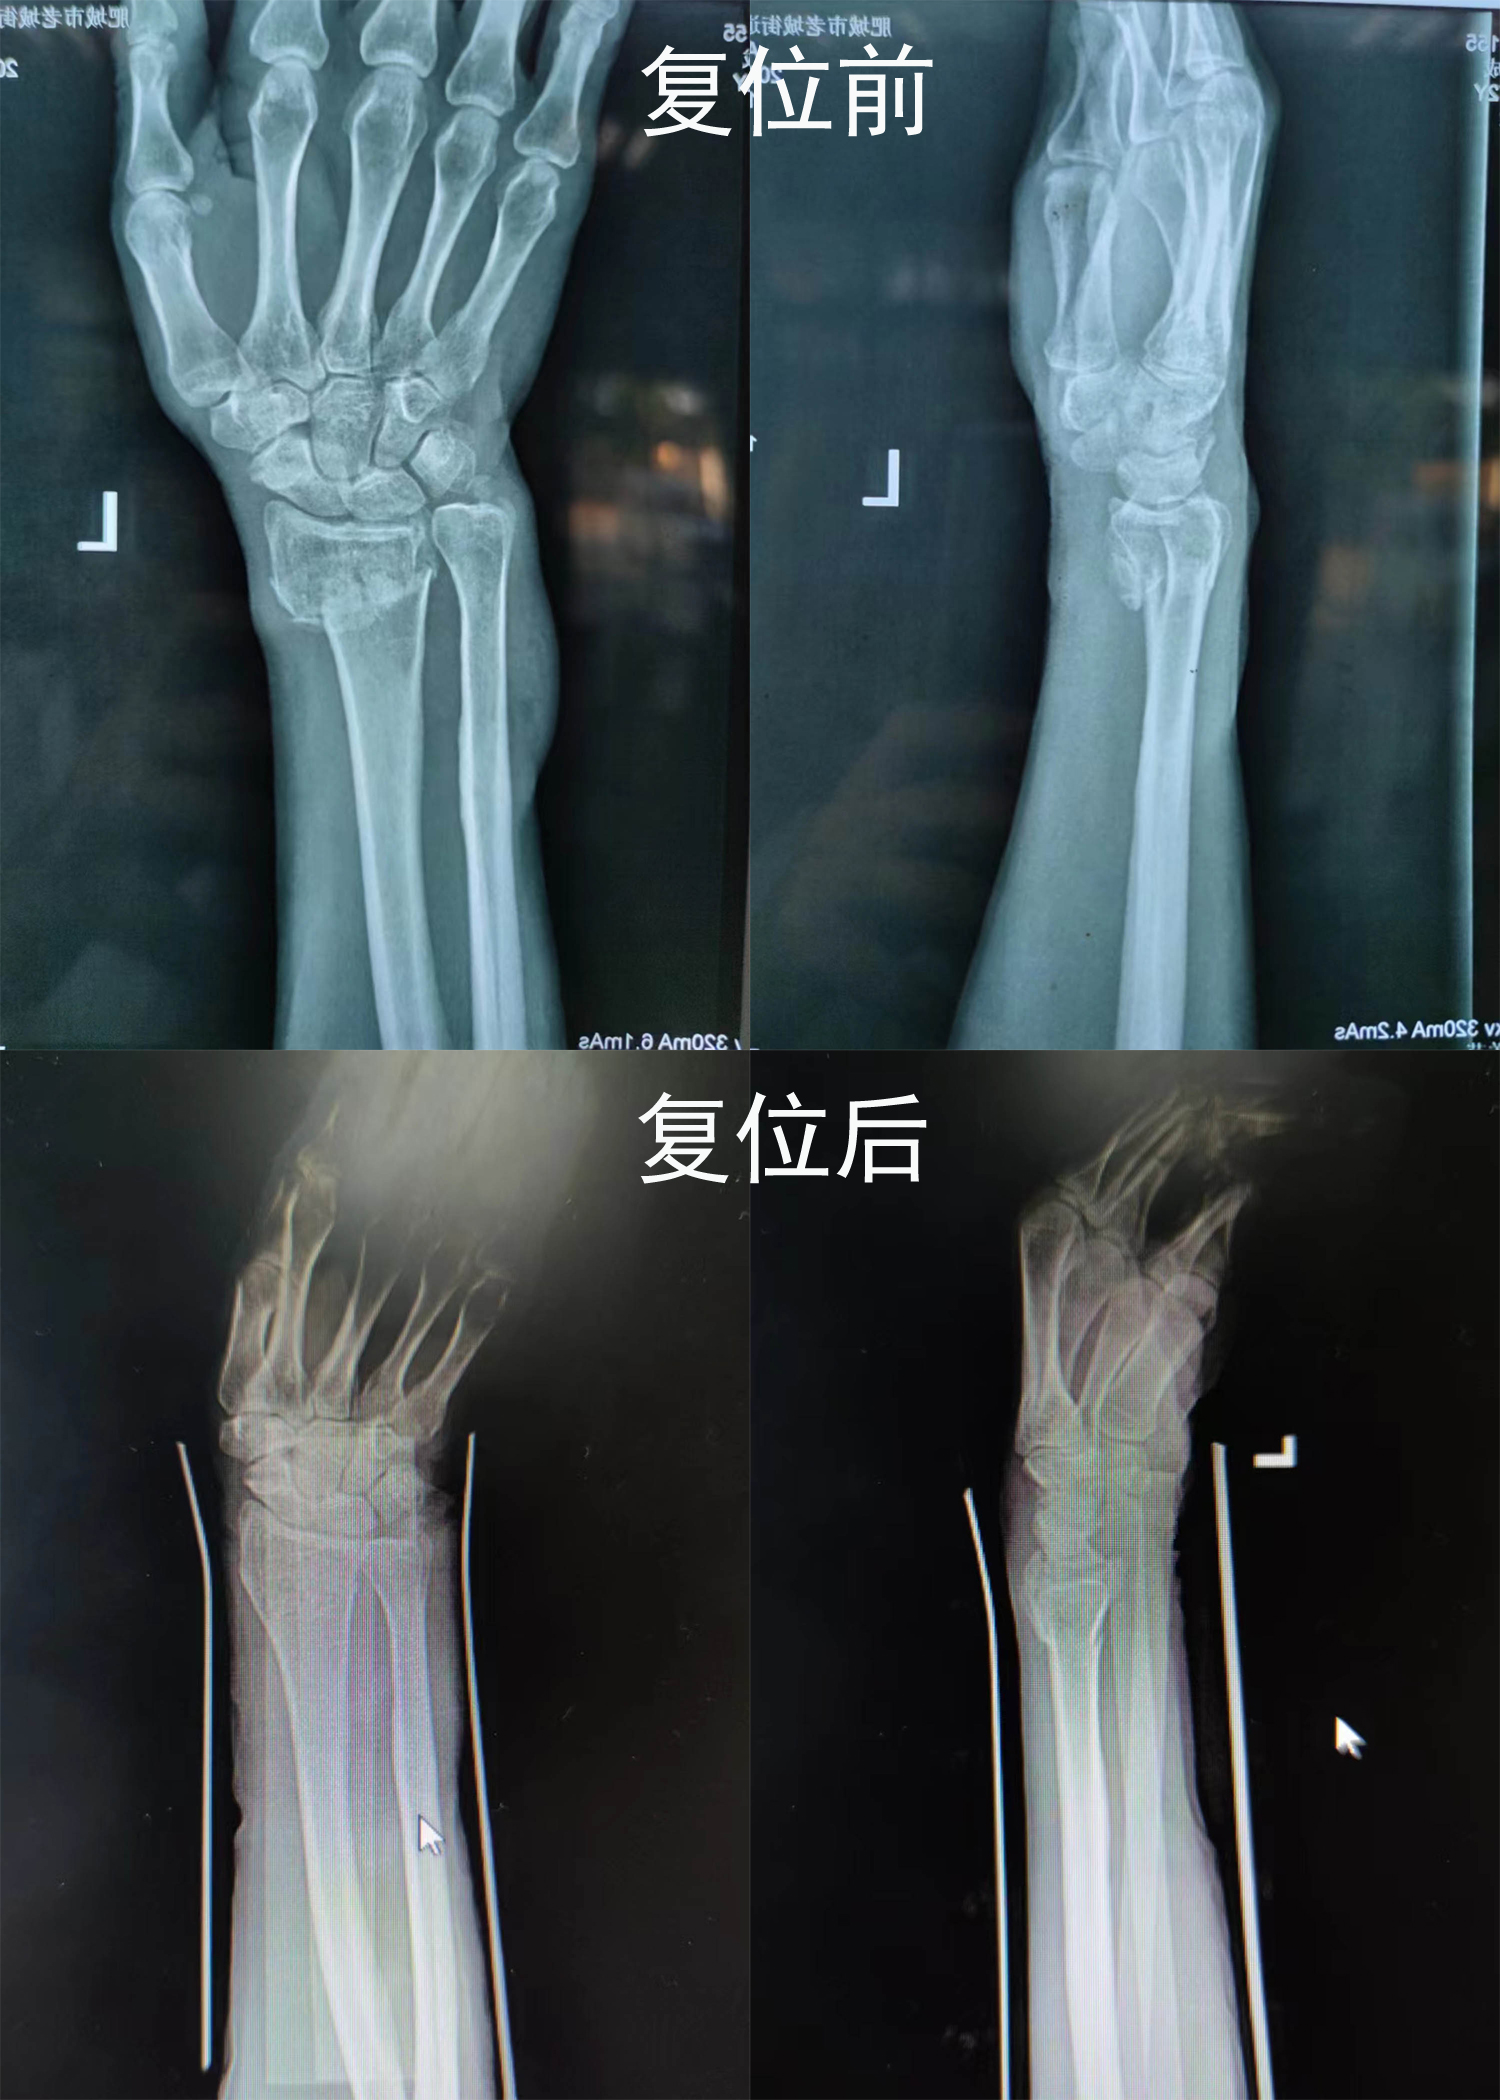

梁氏正骨-杨乐正骨案例